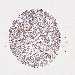

CANCER BREAST CANCER Show tissue menu

BRCA TCGA BRCA VALIDATION PROTEIN EXPRESSION